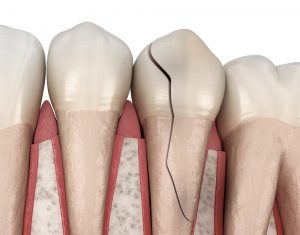

Les origines des abcès dentaires peuvent être variés : une carie dentaire profonde – un traumatisme de la dent – une fracture d’une racine dentaire – une résorption dentaire etc.